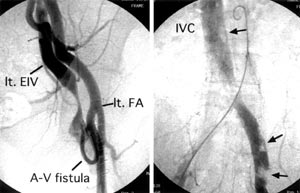

| Fig. 5 Postoperative angiography. →: thrombus,

lt. EIV: left external iliac vein, lt.FA: left femoral artery. |